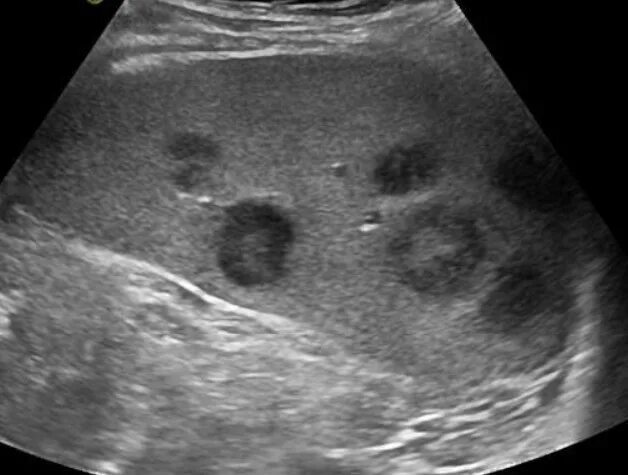

Метастазы при лимфоме